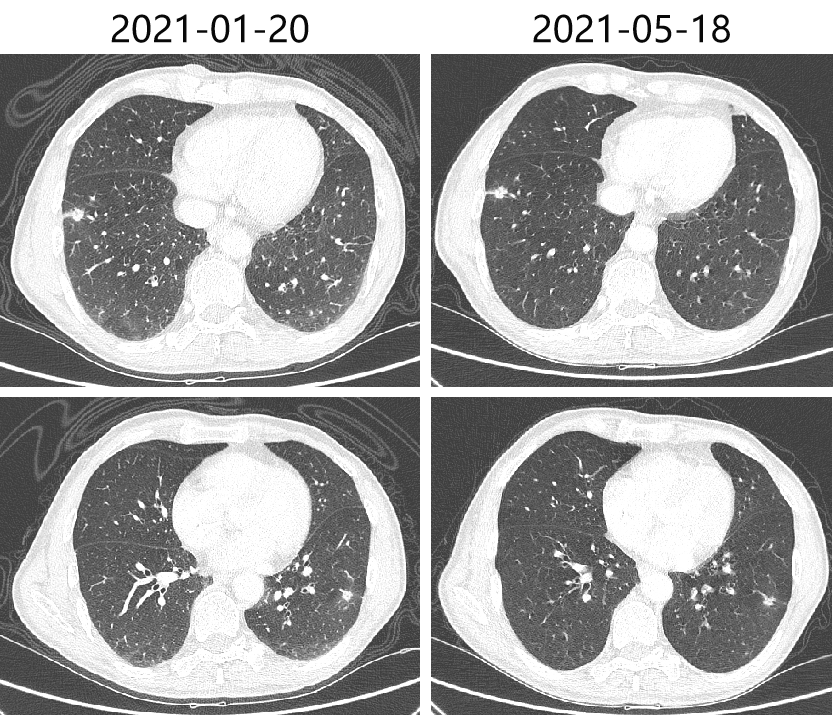

2020-10-30、2021-01-20 复查CT,疗效评价为SD。

2021-05-19头胸腹盆CT,提示双肺多发结节,较前(2021-01-20)大致相仿,考虑转移灶可能;肝左叶占位,考虑转移,较前增大;肝右后叶强化灶考虑转移,较前新增。

肺:肺多发结节,较前(2021-01-20)大致相仿,考虑转移灶可能。

肝:肝左叶占位,考虑转移,较前增大;肝右后叶强化灶考虑转移,较前新增。